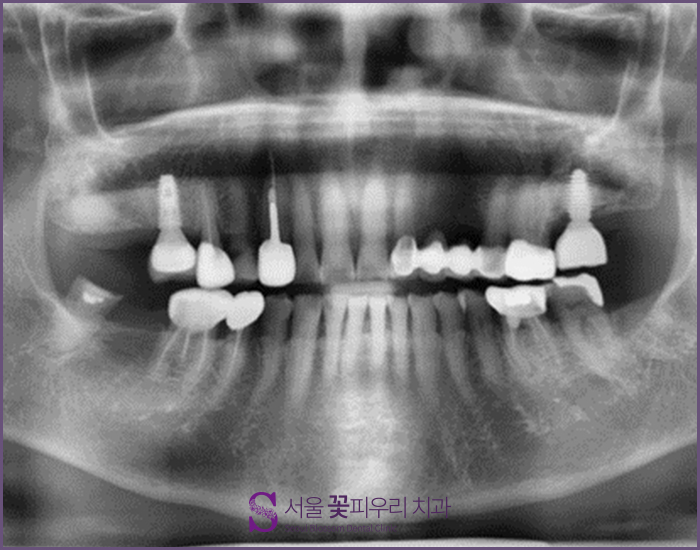

내과와 협의한 후 기존 약을 5일 정도 복용을 중단하고 임플란트 2개를 심기로 결정했습니다 이 사진은 환자분의 3DCT사진입니다. 상하 임플란트 매립을 희망하셨기 때문에 픽스처가 매입할 뼈의 길이와 골질이 충분히 확보되어 있는지 확인했습니다. 위턱은 문제가 없었지만 아래턱 부분에 골밀도가 부족했기 때문에 2회로 나누어 치료를 하게 되었습니다.

아래 사진을 보시면 초록~파랑으로 나타나는 부분은 임플란트를 박기에 골밀도가 충분하고, 붉게 나타나는 부분은 골밀도가 부족한 부분입니다. 한 눈에 봐도 푸르스름한 부분보다는 붉은 부분이 많다는 것을 알 수 있습니다. 따라서 위턱은 1차와 2차 시술을 동시에 진행하였으나 아래턱은 충분한 회복기간을 두고 시술하여 환자들이 만족할 수 있는 대구 임플란트를 완료하였습니다.